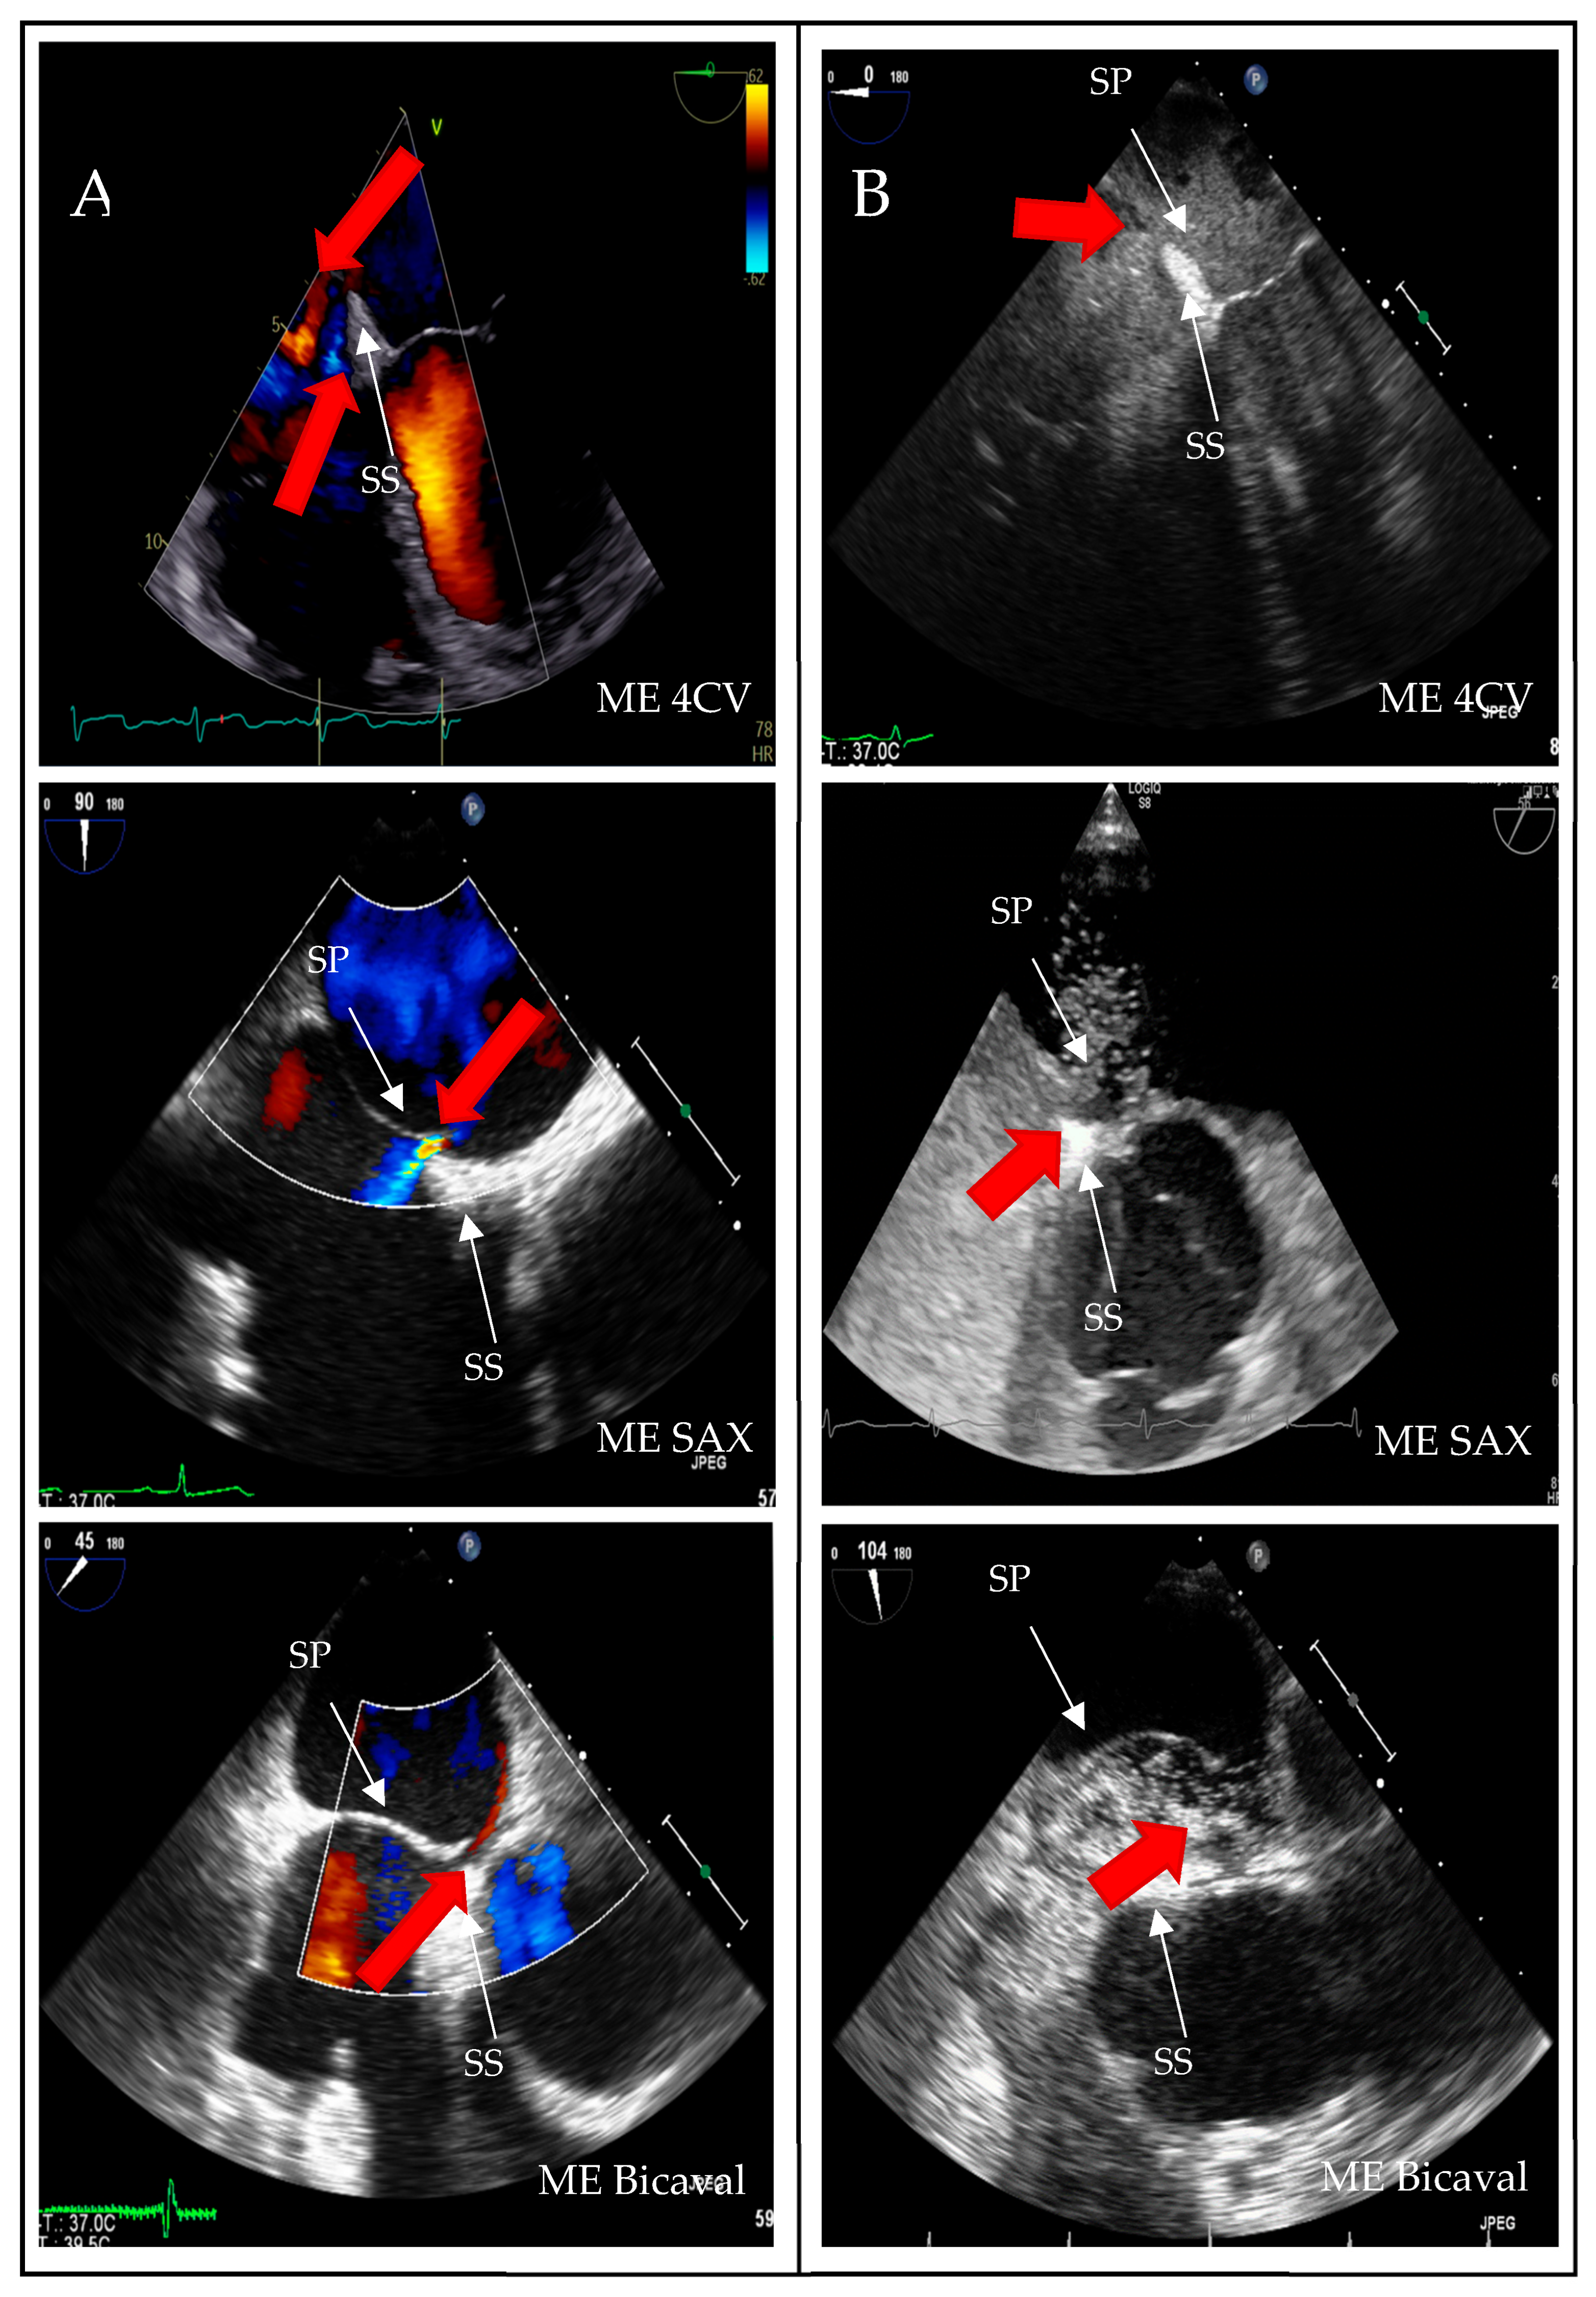

In eleven of the 20 false-positive PFO diagnosis cases, spontaneous contrast was observed in the left atrium (LA). The timing of microbubble appearance in LA serves as a general guideline but is not a reliable indicator. According to Soliman et al., there is significant temporal overlap in the occurrence of bubbles in LA from both a PFO and a proximal interpulmonary shunt [19]. As illustrated, the presence of interatrial septum (IAS) hypermobility significantly influences the timing of bubble crossover. Delayed crossing may result from residual fetal structures in the right atrium, such as the Eustachian valve and the Chiari network. In 5% of patients with PFO, bubbles were detected in LA after six heartbeats.

Examples of residual fetal structures are shown in Figure 4.

This analysis revealed a statistical association between high-grade shunt intensity and PFO diagnosis in the context of IAS hypermobility (p = 0.02). In contrast, remnants of fetal circulation did not significantly impact shunt flow intensity. However, delayed contrast filling of the right atrium remains visible in the imaging sequences, which is critical for the bubble test, as indicated by Johansson et al. [15].

Figure 4. Two-dimensional TOE recordings of fetal anatomical structures as risk factors for PFO. Shown in the ME SAX and ME Bicaval views are (A) a Eustachian valve at the ostium of the inferior vena cava, (B) a Chiari network as a ribbon, fenestrated membrane in the right atrium, and (C) an atrial septal aneurysm with a protrusion into the right and left atrium. VE: Valvula Eustachii, ASA: Atriales Septumaneurysma, ME: Midesophageal, SAX: short axis.